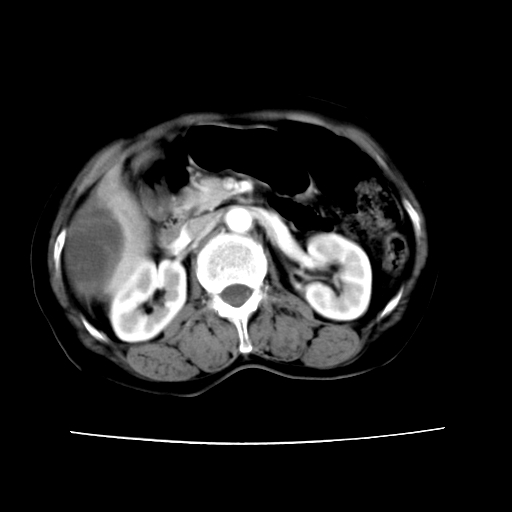

2008-6-10ct平扫

ct增强

6月份ct片显示肝内巨大混杂密度团块,伴包膜下积液(内含液液平面),增强多无明显强化。只能考虑肝占位病变,并肝内、血膜下血肿。肝ca并出血多见,而肝血管瘤并破裂出血少见。

6月份ct片显示肝内巨大混杂密度团块,伴包膜下积液(内含液液平面),增强多无明显强化。只能考虑肝占位病变,并肝内、包膜下血肿。肝ca并出血多见,而肝血管瘤并破裂出血少见。